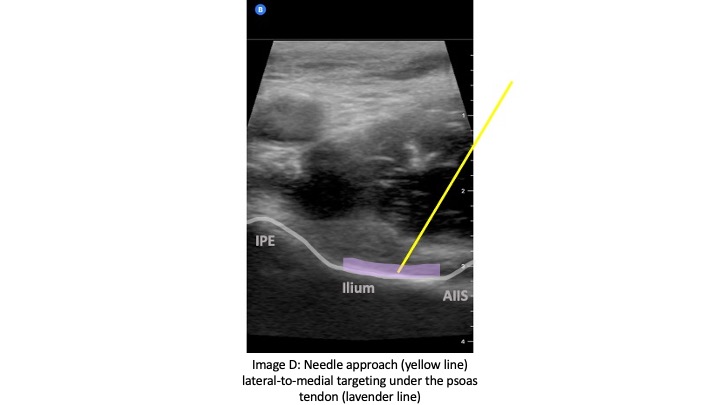

The curvilinear probe is used at an oblique angle parallel to the IL with probe marker to the patient's right side. The linear probe may be used in patients who are thin for better image resolution. Initially, the probe should be positioned inferior to the IL to identify the femoral head (Image B). Then the probe can be moved cranially until the anterior inferior iliac spine (AIIS) and iliopubic eminence (IPE) of the ilium are visualized (Image C). The femoral artery, femoral nerve, iliacus muscle and psoas tendon should be identified. The femoral nerve generally lies right above the psoas tendon on top of the iliacus muscle and is just lateral to the femoral artery. The target is the subfascial plane located underneath the psoas tendon and above the ilium. A 20G or larger long spinal needle or echogenic nerve block needle is inserted in a lateral-to-medial approach until contact with the ilium is made underneath the psoas tendon (Image D). Hydrodissection of the fascial plane using saline initially helps to visualize the correct location before injecting 20 CCs of long-acting anesthetic, such as ropivacaine or bupivacaine with epinephrine. The block has been shown to be effective with a lower concentration of local anesthetic such as 0.25% bupivacaine with epinephrine.

Care must be taken to maintain direct visualization of the needle tip in order to avoid direct injury to the femoral nerve or inadvertent intravascular injection. In a successful block, the local anesthetic should lift the psoas tendon off of the ilium and should track both medially and laterally.1,2 It may be difficult to pierce through the psoas fascia as it lies right up against the bony ilium, so slight rotation of the needle clockwise and counterclockwise can help the needle tip to penetrate the fascia into the target subfascial plane.